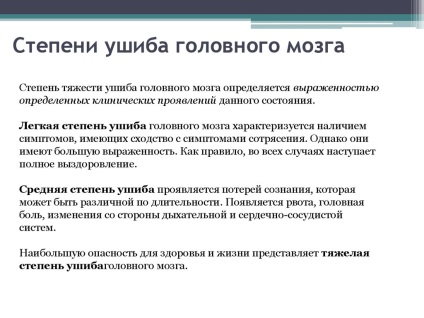

Simptomele variaza in functie de gravitatea prejudiciului rezultat. Luați în considerare Simptomatologia la fiecare grad.

blând

Imagine a prejudiciului într-un mod simplu este după cum urmează:

Durata acestor simptome în timpul contuzie cerebrală nu mai mult de 3 săptămâni ușoară. Toate simptomele de leziuni cerebrale au efecte pozitive, corpul se recupereaza rapid.

Gradul mediu de

Atunci când o leziune a creierului de severitate moderată manifesta simptome similare cu o formă ușoară, o lungime diferită a proceselor de recuperare și apar complicații:

Simptomele si tratamentul leziunilor cerebrale de severitate moderată sunt observate pe parcursul mai multor luni, dispar treptat, dar unele dintre problemele care ar putea să rămână pentru totdeauna.

Atunci când o leziune a creierului intr-o forma severa caracterizata prin simptome parametri însoțitor:

Toate semnele de leziuni cerebrale in dificil de sever pentru a trata. Reabilitarea are loc încet, timp de aproximativ șase luni. tulburări mentale, de vorbire și de mobilitate poate deveni o cauza de handicap a pacientului.